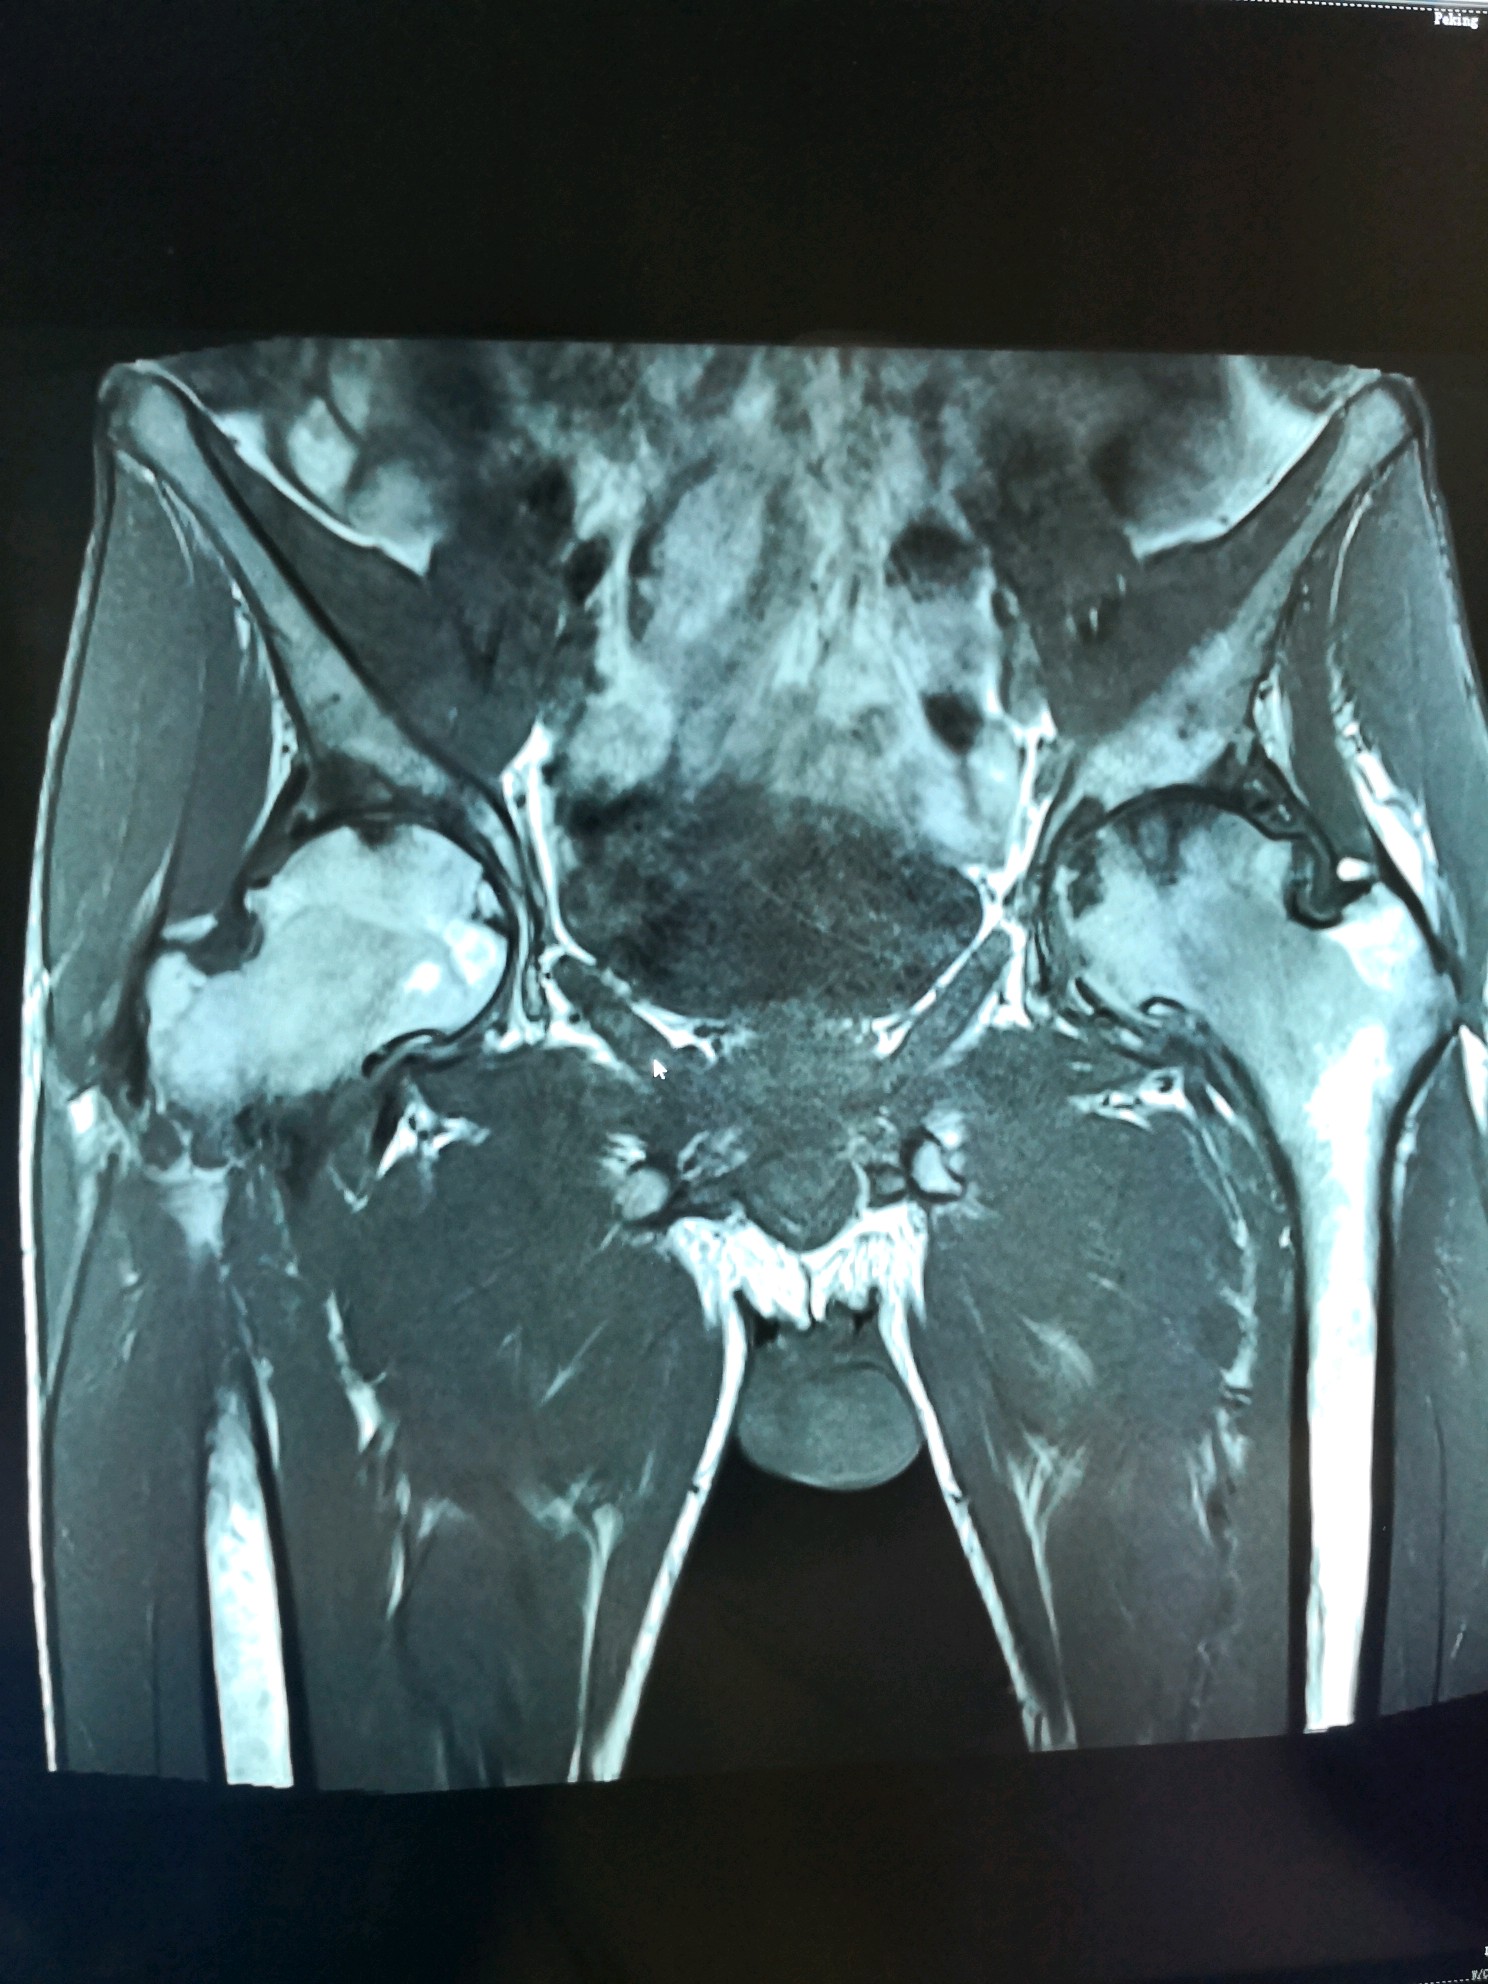

术前双髋MRI

图片发自160医生App